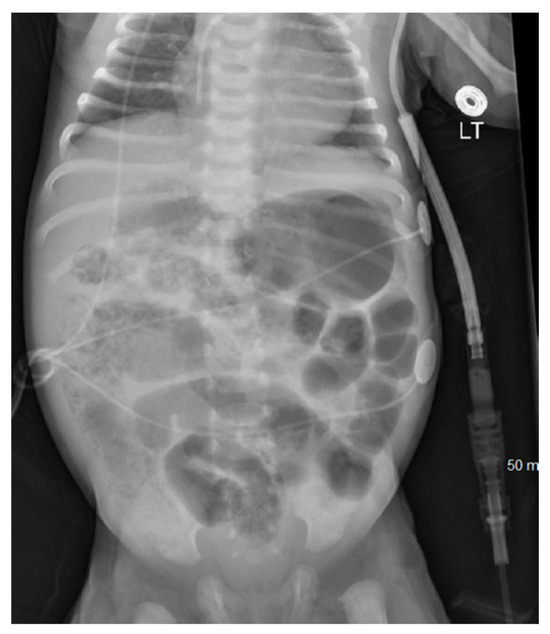

At 6 h of life, exploratory laparotomy confirmed a narrow gastroschisis defect with segmental ileal and colonic atresia. The surgical intervention included a 10 cm segmental ileal resection, colo-colonic anastomosis, ileal–ileal anastomosis, and closure of the gastroschisis defect, with an initial small intestine length of 30 inches. The infant was extubated to room air by 3rd day of life (DOL), and trophic feeds started on DOL 8. The infant had culture-positive sepsis on DOL 10, requiring ceftazidime for ten days and temporary cessation of feedings. Feedings resumed on DOL 15, reaching full enteral feeds by DOL 24. On DOL 25, the infant presented with bloody stools and AXR showing dilated intestines with pneumatosis (Figure 3), indicative of necrotizing enterocolitis (NEC), prompting another period of nil-per-oral status and antibiotic therapy. Feedings restarted on DOL 32 with hypoallergenic infant formula and advanced to full feeds by DOL 37 with the infant bottle feeding all the feeds.

Figure 3. Day 25 abdominal X-ray showing pneumatosis.